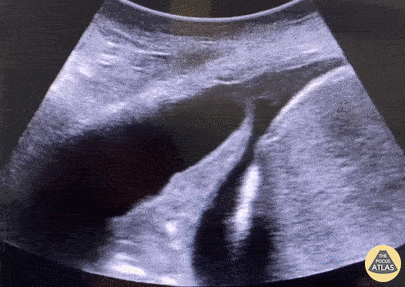

Accumulation de liquide entre les plèvres – pariétale et viscérale.

- Espace anéchogène ou hypoéchogène entre la base pulmonaire et le diaphragme.

- Signe de la colonne vertébrale visible au-dessus du diaphragme grâce à la conduction du son par le liquide.

- Poumon collabé flottant dans le liquide (« signe de la méduse »).

- Anechogène : transsudat simple.

- Complexe ou cloisonné : exsudat ou empyème.

- Échogène : hémothorax.